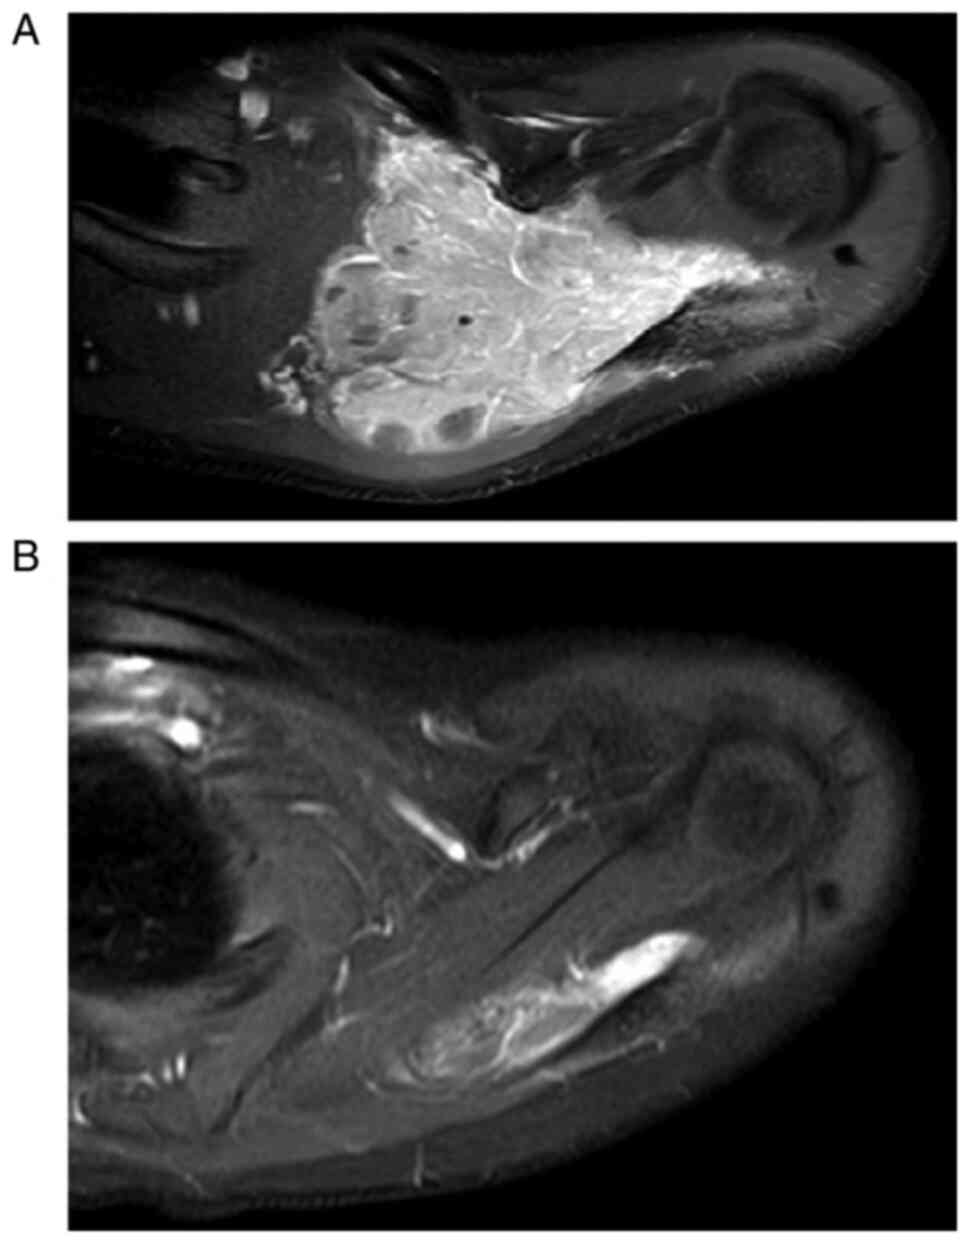

With US, EES usually appears as a heterogenous mass of low echogenicity with intratumor flow signals on a Doppler study. With CT, EES presents as a large sharply demarcated mass with similar intensity to the surrounding muscles. Post-contrast medium enhancement reveals areas of necrosis, while the surrounding viable contour appears enhanced and heterogeneous (20). Calcification is present in only 10% of cases, appearing faint and amorphous (20). With MR imaging, EES has low-to-intermediate signal intensity on T1-weighted sequences and displays high signal intensity on T2-weighted images, with variable post-contrast enhancement (Fig. 1) (20–23). MR imaging is performed prior to biopsy to help determine the optimal biopsy site and to avoid the distortion caused by post-biopsy changes (24). This is also recommended for restaging purposes prior to local control, as the tumor may have receded or progressed during neo-adjuvant chemotherapy (7).

Figure 1.

Axial selective suppression of fat gadolinium-based contrast agent magnetic resonance image of the left shoulder of a 16-year-old woman with extraskeletal Ewing sarcoma (A) pre- and (B) post-chemotherapy treatment.

MR imaging and CT scans are accurate for local staging of malignant bone and soft-tissue tumors (7). However, MR imaging is used more frequently due to its high detection sensitivity for soft tissue contrast, as well as its ability to avoid radiation exposure from CT scans (7).